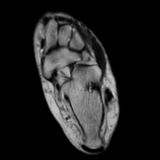

A patient presents with pain in the sole of the foot on both sides, especially on the left side, which occurs with exertion, particularly during the first steps in the morning.

The question of whether there are rheumatic manifestations or whether the complaints are mechanically induced should be clarified.

Mild plantar fasciitis and intraosseous ganglion of the calcaneus